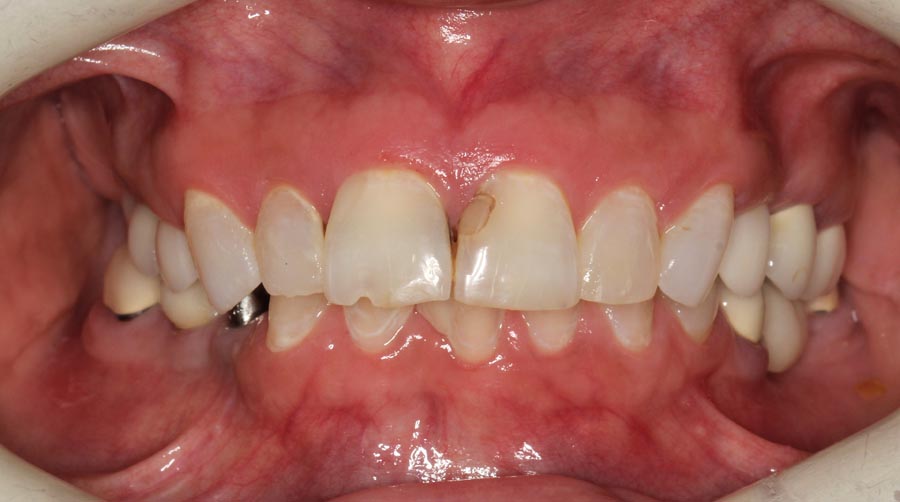

Smile GalleryImplant RestorationsFull Mouth Implant Restoration Full arch zirconia implant bridge (full smile) 1 of 37 Pre-op full smile Pre-op lips retracted Pre-op panoramic x-ray Extraction of strategic teeth Placement of implants Extraction of some remaining teeth after verification of adequate implant stability Occlusal view Post-op panoramic x-ray Immediately fabricated provisional restoration (tissue side view) Immediately fabricated provisional restoration (occlusal side view) Immediate provisional delivered on day of surgery Immediate provisional 2 weeks later Scalloped tissue developed from the provisional at 2 weeks Jig used for making a master impression Provisional in place (full smile) Provisional in place (lips retracted) Provisional in place (right side) Provisional in place (left side) Wax try-in (full smile) Wax try-in (right side full smile) Wax try-in (left side full smile) Wax try-in (full face, lips together) Wax try-in (full smile) Wax try-in (right side) Wax try-in (left side) Wax try-in (lips retracted) Full arch zirconia implant bridge on master cast (frontal view) Full arch zirconia implant bridge on master cast (occlusal view) Implant positions and soft tissue representation on master cast (occlusal view) Soft tissue representation on master cast (frontal view) Full arch zirconia implant bridge (tissue side view) Soft tissues on day of delivery (occlusal view) Soft tissues on day of delivery (frontal view) Full arch zirconia implant bridge delivered (lips retracted) Full arch zirconia implant bridge (lips retracted, close up) Post treatment panoramic x-ray Full arch zirconia implant bridge (full smile)